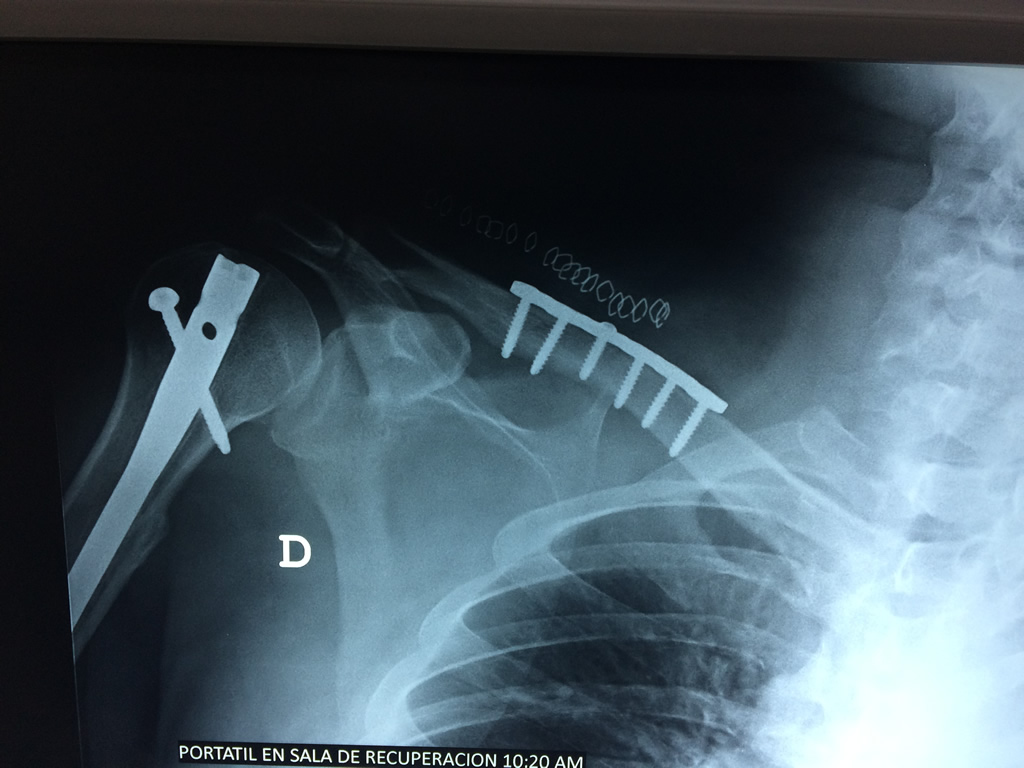

La clavícula es un hueso largo, con forma de "S" itálica, situado en la parte anterosuperior del tórax. Junto con la escápula forman la cintura escapular. Se puede palpar por toda su longitud y se extiende del esternón al acromion de la escápula, siguiendo una dirección oblicua lateral y posterior.

Se considera el único medio de unión entre el miembro superior y el tórax. A pesar de su aspecto, similar al de un hueso largo, posee una estructura semejante a la de un hueso plano, ya que carece de epífisis y de diáfisis, lo que la harían entrar dentro de la clasificación de hueso largo. Carece de un canal medular propiamente dicho.